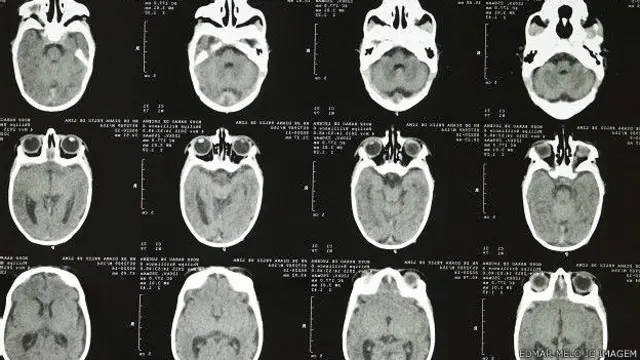

"Cuando los bebés nacen los médicos miden el perímetro encefálico, la medida del contorno de la cabeza del bebé en su parte mayor", explicó Rocha.

"Consideramos microcefalia un perímetro igual o menor de 33 cm. Lo normal para un bebé es entre 34 y 37 cm, dependiendo de en qué semana de gestación nace".

"También pedimos una tomografía y un análisis de sangre. Cuando ocurre un proceso de infección, que es lo que sospechamos, entre el primer y cuarto mes de embarazo, el agente que causa la infección provoca un proceso inflamatorio que deja cicatrices en el cerebro del bebé", añadió la pediatra.

"Esas áreas están muertas, calcificadas, el cerebro no logra crecer bien sino en forma desorganizada y aparecen otros problemas en su estructura".